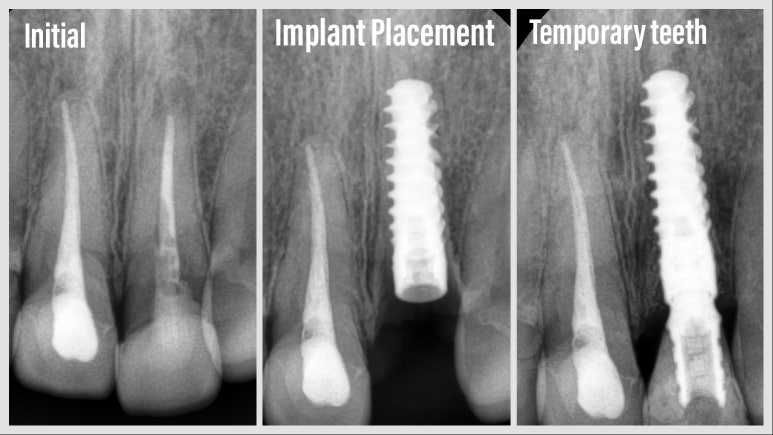

수술 전 - 임플란트 수술 후 - 임시치아 장착 후 엑스레이 사진

이런 경우 임플란트 수술에 있어서 1차 원칙, 가능한 한 최소침습적인 방식으로 발치를 하고, 당일 바로 임플란트 나사를 식립한답니다. 이 환자분의 경우 발치 후 즉시 식립 시 초기 고정을 얻기 쉬운 #스트라우만 BLX 임플란트를 사용하여 수술을 진행하였답니다.